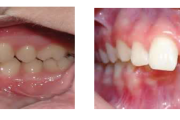

Lutipudelikaariese kahjustused

Lutipudelikaaries

Ravijärgne seis. Jäävhammas on täielikult lõikunud.